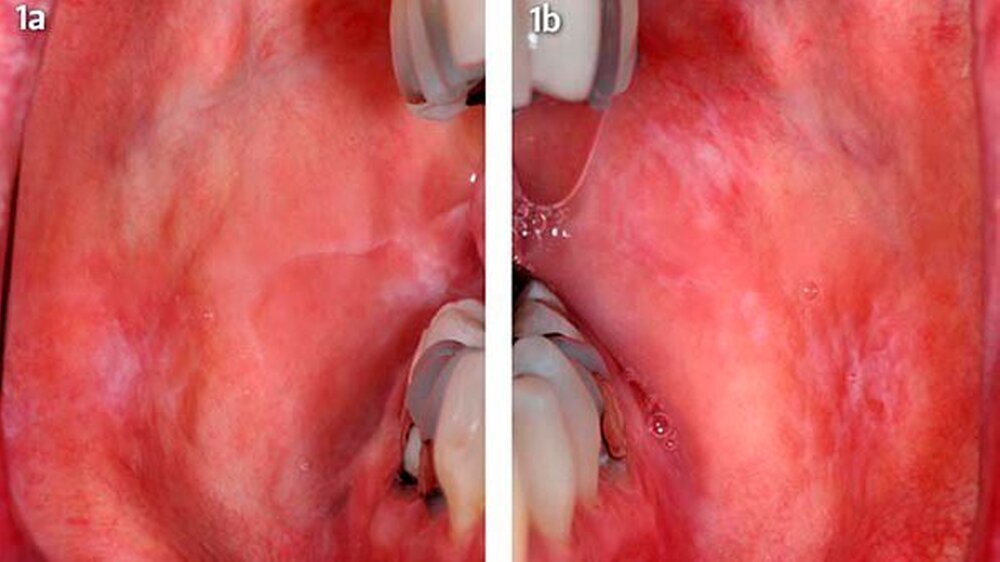

Eine 47-jährige Frau stellte sich Anfang 2012 in der Sektion für Klinische und Experimentelle Orale Medizin am Universitätsklinikum Leipzig wegen länger bestehenden typisch weißlichen Schleimhautveränderungen ohne subjektive Beschwerden vor. Nebenbefundlich bestand eine mit L-Thyroxin behandelte Hypothyreose. Beidseits im Planum buccale und in der Kieferwinkelregion rechts zeigten sich sogenannte Wickham-Streifungen mit stellenweise plaqueartigen Inseln sowie einer schwarzen Pigmentierung vestibulär von Zahn 47 (Abb. 1a, b).

Dieser Befund passte zu einer erosiv-entzündlichen Veränderung der Mukosa. In der Biopsie der Wangenregion rechts zeigte sich eine geringradig regeneratorische Epithelhyperplasie. Als Diagnosen wurden ein kombiniert retikulär-erosiver Lichen sowie eine lichenoide Kontaktläsion regio 47 und eine Einlagerung von exogenen Pigmenten («Amalgamtätowierung») in regio 47 beschrieben. Vor einem Austausch der Füllungen wurde der Patientin eine erneute Epikutantestung empfohlen. Hier fand sich eine polyvalente Sensibilisierung zusätzlich auf Epoxidharz, Amalgam (mit Zink) und Quecksilber (II)-amid-chlorid sowie vier der getesteten Proben (Tab. 1).

In den Nachuntersuchungen sechs Monate nach Entfernung der Amalgamfüllungen zeigte sich ein deutlicher Rückgang der lichenoiden Effloreszenzen (Abb. 5a, b). In regio 47 distal bestand ein retikulärer Lichen planus. Die plaqueartigen Inseln im Planum buccale und die großflächigen Wickham-Streifungen sind weitgehend zurückgegangen. Die Patientin befindet sich weiterhin in einem engmaschigen Recall.